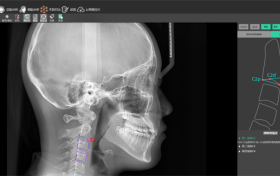

当AI骨龄分析遇见低剂量口腔CT:儿童正畸的双重精准保障

口腔健康,影响着孩子的自信与未来。很多家长,在孩子需要正畸治疗的时候,都会担心:拍片子辐射大不大?孩子的骨龄发…